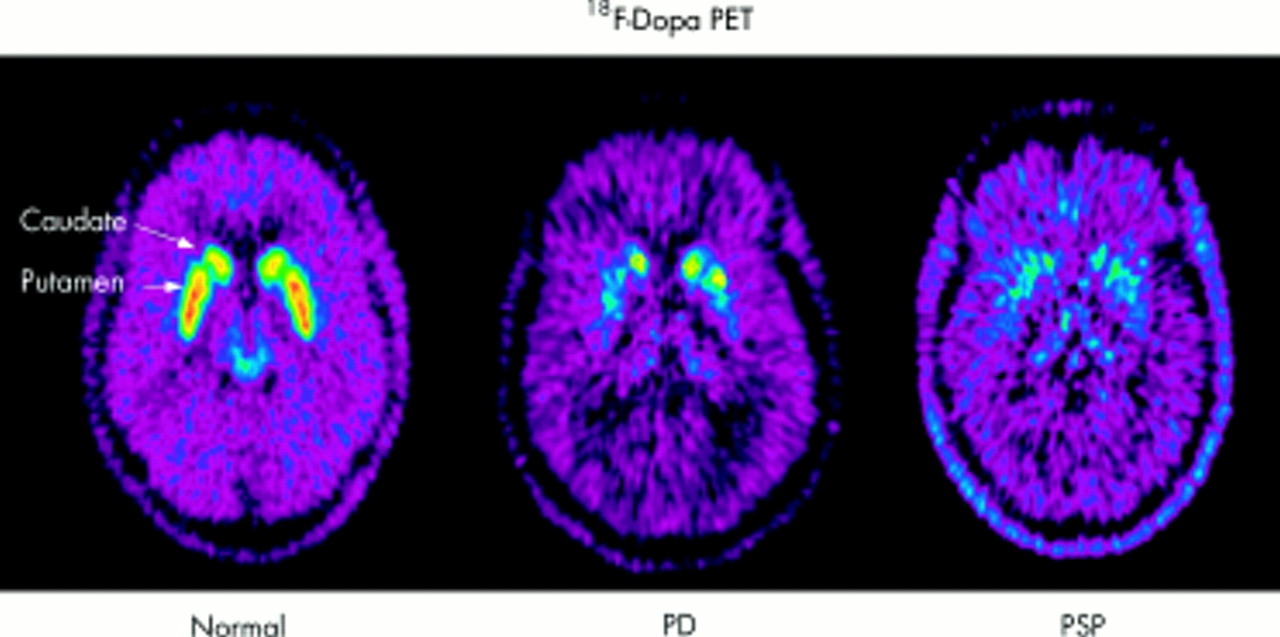

La malattia di Parkinson è una malattia progressiva che si sviluppa quando il cervello perde cellule che producono la dopamina – una sostanza chimica che controlla ricompensa e piacere e regola anche il movimento e le risposte emotive.